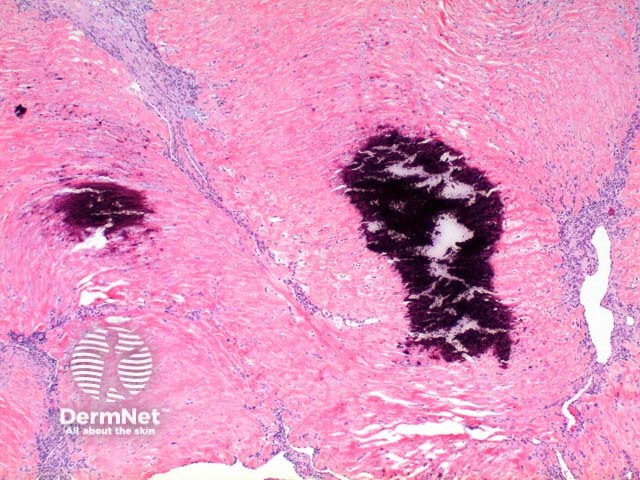

Low power view of myofibroma demonstrates a well defined multinodular tumour arising in the deep dermis or subcutis (Figure 1). Also at low power a branching ‘staghorn’ like pattern of blood vessels can be seen between the tumour nodules (Figure 2). Areas of calcification can often be seen (Figures 2, 3 and 5). The tumour nodules are comprised of a spindle cell proliferation with short plump nuclei (Figures 4,5 and 6). A basophilic tinge in the spindled peripheral component of the nodules is evident (Figures 7 and 8). Sclerotic collagen in the centre of the tumour nodules gives a biphasic appearance to the tumour (Figure 9).